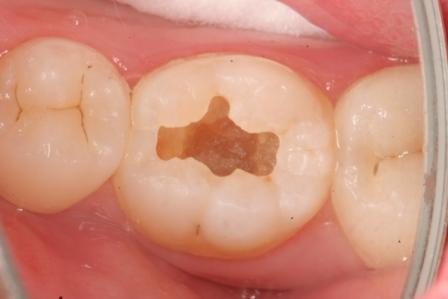

下顎7番の頬側歯茎部カリエスの原因 2025.06.04